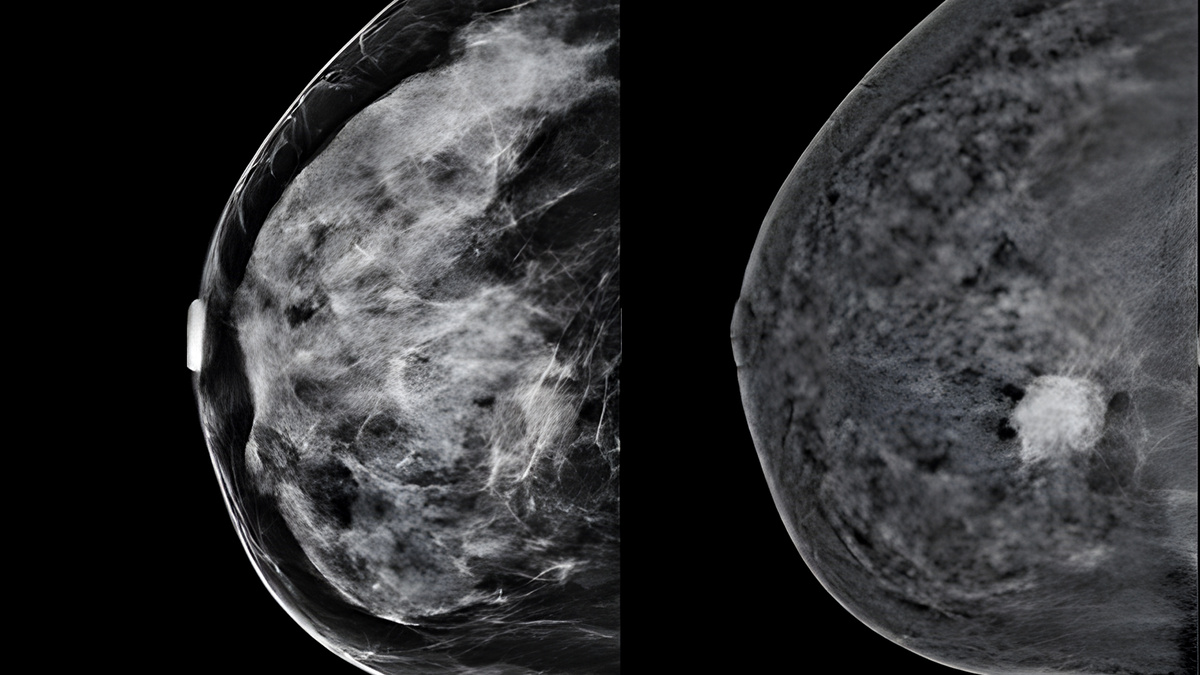

Железа высокой плотности (Тип C и D ACR) способна маскировать наличие опухолевых образований при проведении стандартной рентген-маммографии, используемой для скрининга.

Вероятность пропустить злокачественную опухоль молочной железы на маммографии у пациенток с железой типа A составляет около 2%.

У женщины с железой высокой плотности риск пропуска патологии составляет уже порядка 60%.

Слева стандартный снимок железы высокой плотности. Справа комбинированное изображение этой же железы, полученное с помощью двуэнергетической контрастной маммографии. На снимке отчетливо видно образование, незаметное на стандартной маммографии.